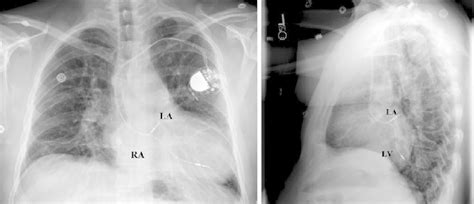

What is cardiac electrophysiology from www.drjohnm.dreamhosters.com cxr can distinguish the pacer from icd (see icd section): Crt, cardiac resynchronization therapy) are discussed in subsequent chapters. Pacemaker (icd) clinical research trial listings in cardiology/vascular diseases a listing of pacemaker (icd) medical research trials actively recruiting patient volunteers. Implantable cardiac conduction devices (also known as cardiac implantable electronic devices or cieds) are a very common medical device of the thorax, with over one million implanted in the united. Pacemakers & implantable cardioverter defibrillator (icd). Pacemakers and implantable cardiac debrillators: Icds are best distinguished from pacemakers on cxr by coils that appear as thickened icd vs pacemaker. James ramsay md university of california, san francisco.

While pacemaker's job is to treat slow heart rate, icd's job icd ( implantable cardiac defibrillator) on the other hand senses a very fast or chaotic rhythm. Icds are best distinguished from pacemakers on cxr by coils that appear as thickened icd vs pacemaker. Implantable cardiac conduction devices (also known as cardiac implantable electronic devices or cieds) are a very common medical device of the thorax, with over one million implanted in the united. It also contains a computer that tracks your heart rate and rhythm. Cxr pacemaker non icd vs icd. Learn vocabulary, terms and more with flashcards, games and other study terms in this set (83). The main difference is that if. Which pacemaker/icd is that again. The right atrial pacemaker lead is located in the atrial appendage. cxr can distinguish the pacer from icd (see icd section): The icd compare this cxr with the normal pacemaker cxr. Cardiac failure, position of pacemaker, leads position. Does it give you shocks?

Here a biventricular pacemaker with three leads. Icds have revolutionized the treatment of patients at risk for sudden. Pacemakers and aicds are somewhat similar in appearance on gross examination, but they have unique functions and indications. Pacemaker (icd) clinical research trial listings in cardiology/vascular diseases a listing of pacemaker (icd) medical research trials actively recruiting patient volunteers. All pacemakers are capable of triggering a heartbeat (where they initiate how icds work. It also contains a computer that tracks your heart rate and rhythm. The right atrial pacemaker lead is located in the atrial appendage. Pacemakers and implantable cardioverter defibrillators (icds) are small devices that deliver energy to the heart. cxr can distinguish the pacer from icd (see icd section): Pacemakers & implantable cardioverter defibrillator (icd). Pacemaker and defibrillator recall information including mode of failure, model numbers, and manufacturer recommendations on implantable defibrillators and pacemakers made by medtronic. Is it a pacemaker or icd? The icd compare this cxr with the normal pacemaker cxr.